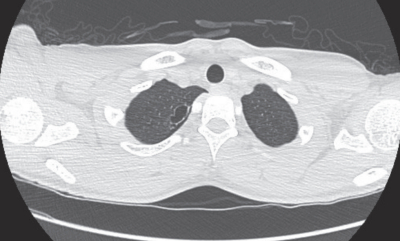

既往歴:2か月前に労作時の息切れが急に出現し軽快したが、心配になり受診した。自宅近くの病院で胸部CTを施行された。その時の胸部単純CTを別に示す。

2か月前